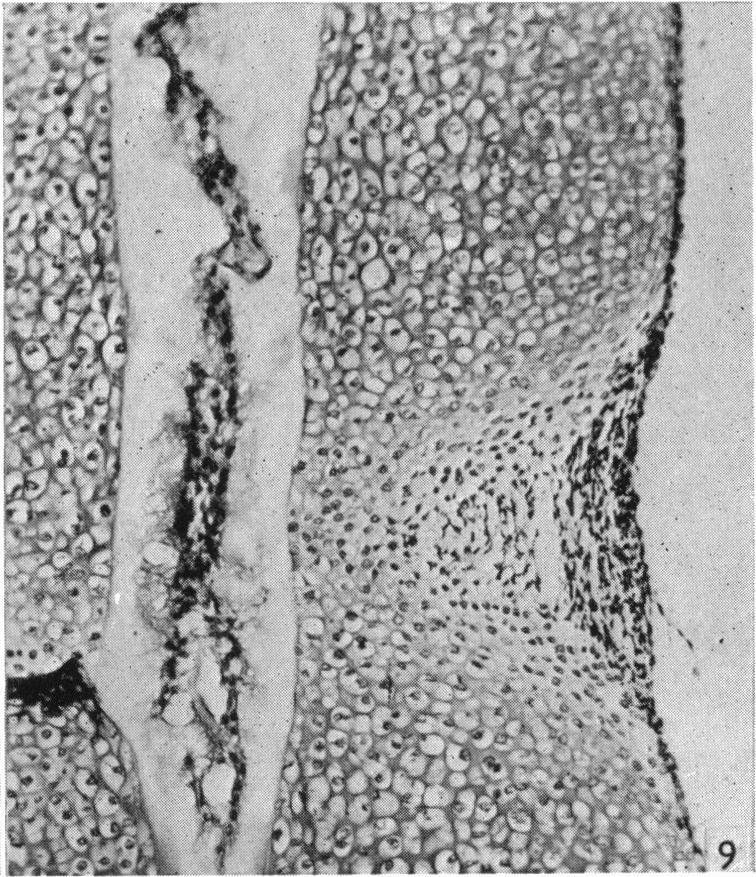

Observations on the prenatal development of the intervertebral disc in man.

J Anat. 1951 Jul;85(3):260-74.